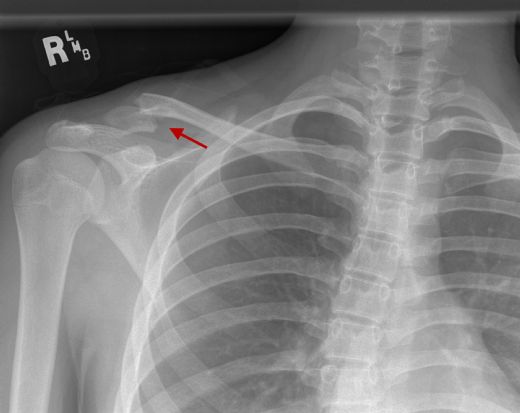

Köprücük Kemiği Kırılması Belirtileri ve Tedavisi

Köprücük kemiği kırılması, genellikle düşme veya darbe sonucu oluşan yaygın bir yaralanmadır. Bu durumun belirtileri arasında ani ağrı, şişlik, hareket kısıtlılığı ve şekil bozukluğu yer almaktadır. Tedavi yöntemleri, kırığın ciddiyetine göre istirahat, atel kullanımı ve gerektiğinde cerrahi müdahaleyi içerir. Erken tanı ve uygun tedavi süreci, iyileşmeyi hızlandırır.

Köprücük Kemiği Kırılması: Belirtileri ve Tedavisi Köprücük kemiği (klavikula), göğüs kafesinin üst kısmında, sternum ile omuz arasında yer alan ve vücut yapısında önemli bir rol oynayan bir kemiktir. Köprücük kemiği, birçok kas ve bağ ile desteklenir ve bu nedenle vücudun hareketliliği için kritik bir öneme sahiptir. Bu makalede, köprücük kemiği kırılmasının belirtileri, nedenleri ve tedavi yöntemleri ele alınacaktır. Köprücük Kemiği Kırılmasının Nedenleri Köprücük kemiği kırılması, genellikle aşağıdaki durumlar sonucunda meydana gelir:

Bu gibi durumlar, köprücük kemiğinin kırılmasına yol açabilir ve acil tıbbi müdahale gerektirebilir. Köprücük Kemiği Kırılmasının Belirtileri Köprücük kemiği kırıldığında ortaya çıkan belirtiler arasında şunlar bulunmaktadır:

Bu belirtiler, köprücük kemiği kırılması durumunda hastaların acil tıbbi yardım alması gerektiğini gösterir. Tedavi Yöntemleri Köprücük kemiği kırılması tedavisi, kırığın ciddiyetine ve türüne bağlı olarak değişiklik göstermektedir. Genel olarak uygulanan tedavi yöntemleri şunlardır:

İyileşme Süreci Köprücük kemiği kırılmalarında iyileşme süreci genellikle 6-12 hafta arasında değişmektedir. Bu süre, kırığın tipine, tedavi yöntemine ve hastanın genel sağlık durumuna bağlı olarak farklılık gösterebilir. İyileşme sürecinin başarılı olması için hastaların doktorun önerilerine uyması ve fizik tedavi programlarına katılması önemlidir. Sonuç Köprücük kemiği kırılması, yaşam kalitesini olumsuz etkileyen bir durumdur. Belirtileri tanımak ve zamanında tıbbi yardım almak, tedavi sürecinin başarılı bir şekilde ilerlemesi açısından kritik öneme sahiptir. Kırıkların tedavisi için uygun yöntemlerin belirlenmesi ve hastaların iyileşme süreçlerine dikkat etmeleri, sağlıklı bir geri dönüş sağlayacaktır. Hastaların, köprücük kemiği kırılması gibi durumlarla karşılaşmamak adına spor yaparken uygun güvenlik önlemlerini almaları ve dikkatli olmaları önem arz etmektedir. |